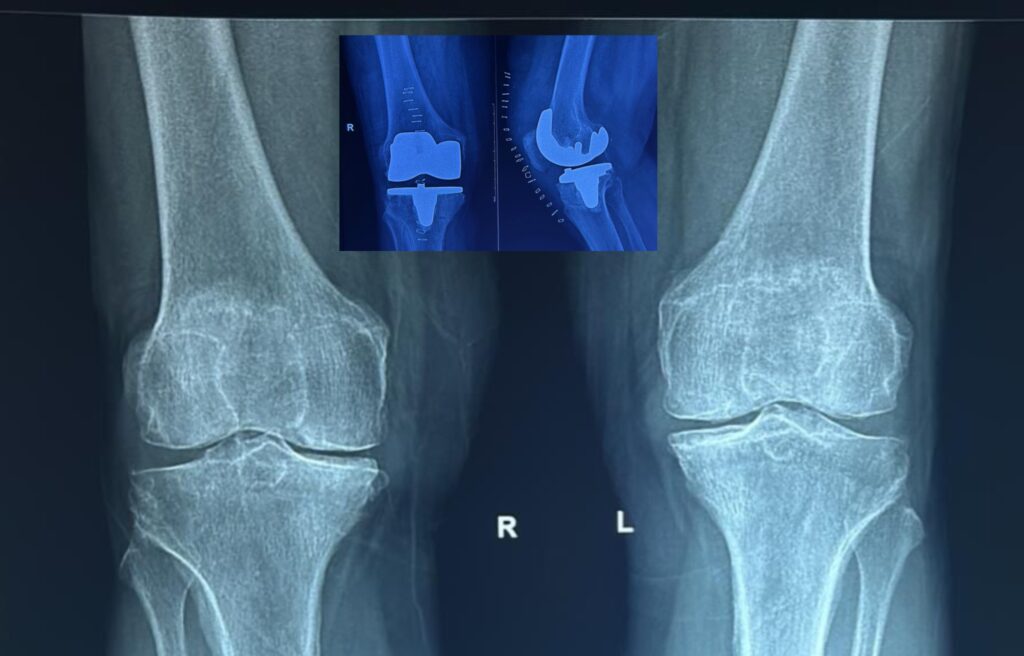

Knee Replacement Recovery in Gurgaon: How Physiotherapy Turns Pain Into Pain-Free Movement

The surgical procedure replaces the damaged joint effectively. However, Physiotherapy After Knee Replacement is essential for complete Knee Replacement Recovery in Gurgaon, preventing stiffness and restoring function for daily activities amid the city’s dynamic lifestyle.